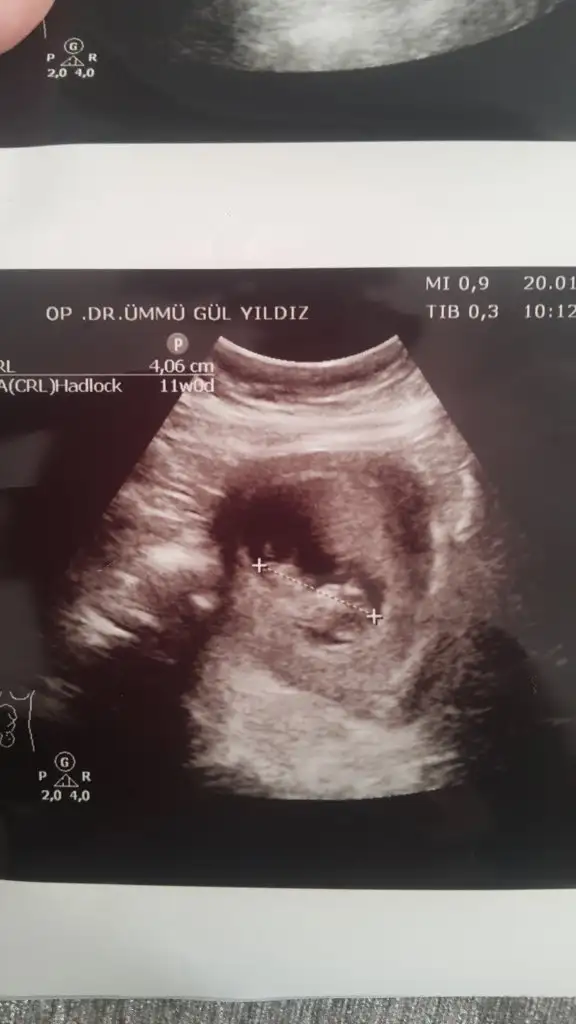

mrhaba lütfen yorumlarmisiniz sizce kızmı erkekmi bi arkadas icin soruyorum

Sevgili İkra,

Yorumlarsan çok sevinirim. ☺️❤️